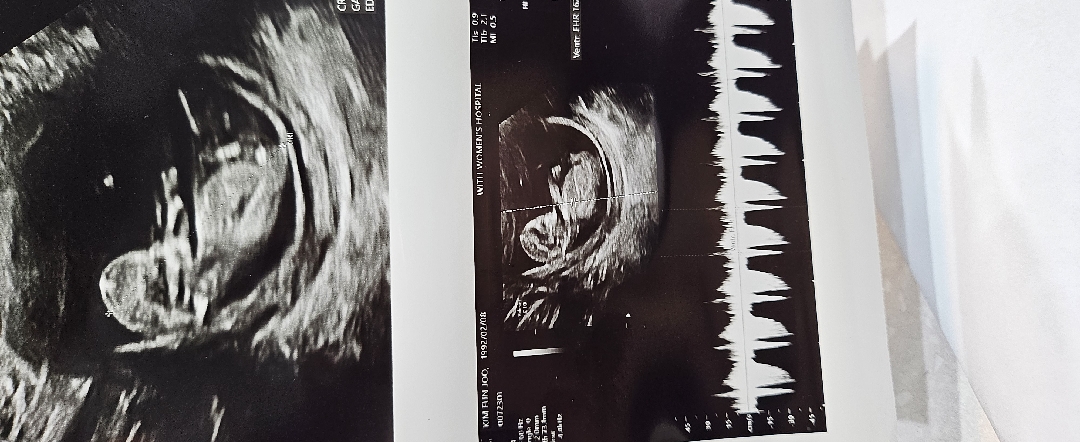

12주 초음파봐주세요!

12주 기형아검사하고왔어요! 각도법이란게 있어서 궁금해서올려봅니다ㅎ 참견 마구마구부탁드려요